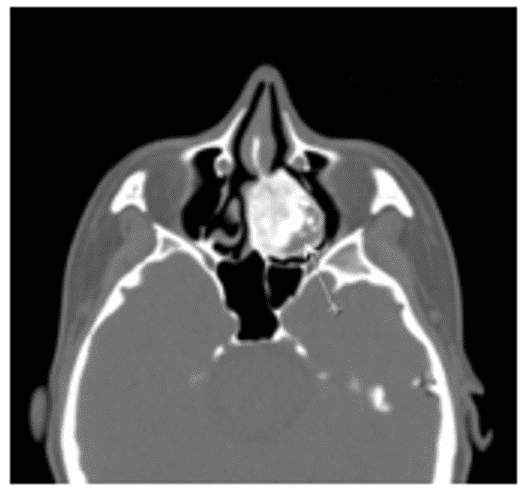

Остеобластома на КТ обычно представлена сочетанием плотной кости и участков затемнения (рисунок 4).

Рис. 4. КТ черепа, аксиальная плоскость. Гигантская остеобластома, распространяющаяся в правую орбиту, полость носа и переднюю черепную ямку

Данные КТ позволяют определить признаки локально агрессивного роста остебластомы, место ее исходного роста, наличие/отсутствие распространения опухоли за пределы околоносовых пазух.